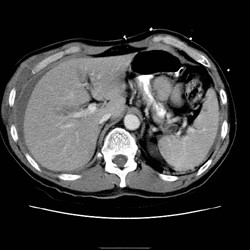

RADIOLOGY: PANCREAS: Case# 47: PANCREATIC TRANSECTION. 32 year old female s/p MVA one day prior now with elevated amylase and lipase. There is a large amount of ascites. There is disruption of the pancreatic head just anterior to the portal vein confluence. Pancreatic transection is uncommon and associated with a high mortality since it is often clinically occult. In complete transection, CT images may show two ends separated by low-density fluid that remains relatively confined to the anterior pararenal space in the immediate post-injury period. Pancreatic enlargement, fluid collections, and lucent defects may also be present. In incomplete transections, tissue displacement may be minimal, and lacerations may be difficult to identify, however, but may be suggested by unexplained thickening of the anterior renal fascia.